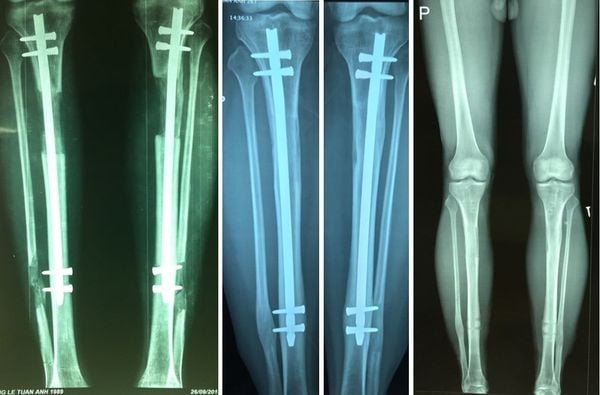

Các bạn nữ muốn biết mình còn phát triển chiều cao không thì phương pháp chụp X-quang xương chân là cách chính xác nhất tới thời điểm hiện tại. Sau khi có kết quả X-quang, các bác sĩ sẽ xác định tình trạng sụn tăng trưởng (vị trí của sụn tăng trưởng nằm ở giữa hai đầu xương dài) và đưa ra đánh giá liệu bạn vẫn có khả năng tăng chiều cao tiếp hay không. Nếu sụn tăng trưởng vẫn được sản xuất liên tục và dần dần chuyển hóa thành xương, giúp xương kéo dài tiếp tục thì bạn hoàn toàn vẫn còn cơ hội để gia tăng chiều cao.